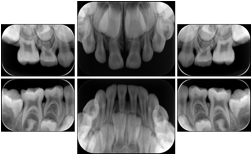

3. A dental provider wishes to capture a series of DICOM IO images for the patient’s dentition. The tooth morphology, teeth are divided into molars, premolars, canines and incisors, and a number of images for each jaw. The anatomic information was captured utilizing the triplet of schema. This standard code sequence is based on ISO 3950-2010, Dentistry - Designation system for teeth and areas of the oral cavity.

Every IO image should have anatomic information either through the primary or modifier sequence.

In most standard cases, images are oriented in structured layouts. These structured displays are useful to be shared between providers for reference purposes.

Table OO.1.1-1 shows structured display standard templates, where Viewset ID is based on the Japanese Society for Oral and Maxillofacial Radiology (JSOMR) classification provided by JIRA (Japan Medical Imaging and Radiological Systems Industries Association, www.jira-net.or.jp). Expected or typical teeth to be imaged location, region and designation codes are based on ISO 3950-2010, Dentistry - Designation system for teeth and areas of the oral cavity. For all the hanging protocols listed in OO.1.1-1, the value to use for Hanging Protocol Creator (0072,0008) is "JSOMR" and the value to use for Hanging Protocol Name (0072,0002) does not include "JSOMR" (e.g., "DL-S001A", not "JSOMR DL-S001A").